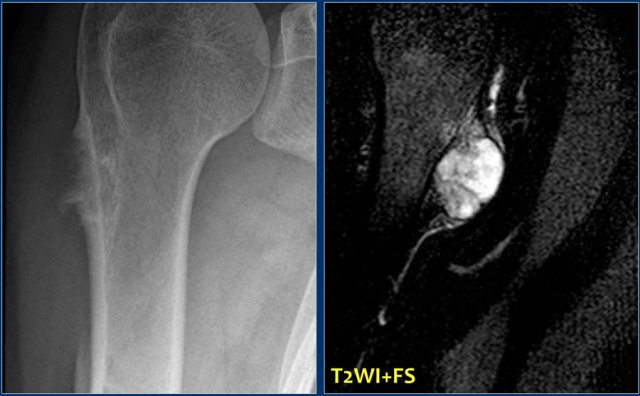

Here a patient with a broad-based osteochondroma.

Notice that the cortical bone extends into the lesion.

This feature differentiates it from a juxtacortical tumor.

Here a patient with a broad-based osteochondroma with extension of the cortical bone into the stalk of the lesion.

Notice the lytic peripheral part with subtle calcifications.

This part corresponds to a zone of high SI on T2-WI with FS on the right.

This represents a thick cartilage cap.

This is an example of progression of an osteochondroma to a peripheral chondrosarcoma.